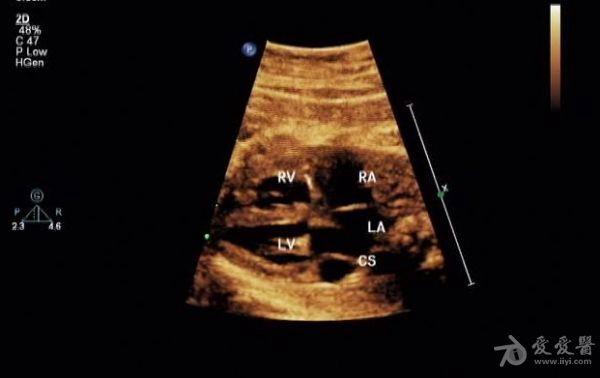

胎儿永存上腔静脉

冠状静脉窦增宽约

0.8 cm

,心底部三血管切面显示肺动脉左侧管腔样结构,频谱显示为静脉频谱。